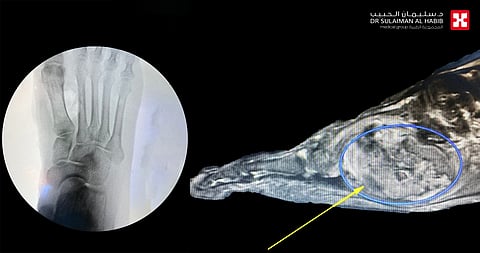

ذكر ذلك الأستاذ الدكتور فوزي الجاسر استشاري جراحة العظام والمفاصل رئيس الفريق الطبي المعالج للحالة، الذي قال أن المريض راجع المستشفى بعد معاناة طويلة مع أعراض حادة شملت الآلام ومحدودية القدرة على الحركة، وتفاقمت هذه الأعراض مع تزايد حجم الورم، وفور وصوله إلى المستشفى خضع لحزمة من الفحوصات الدقيقة وقد بينت صور الأشعة السينية والرنين المغناطيسي مع الصبغة، وجود ورم موضعي كبير في باطن القدم الأيمن، وهو متزايد وملتف حول الأوتار والأوعية الدموية، وأخضع الفريق الطبي الحالة إلى دراسة، وخلص إلى أن التعامل الأمثل معها هي إزالة هذا الورم، وبعد إتخاذ الترتيبات اللازمة خضع المريض لعملية جراحية دقيقة، تم فيها استئصال الورم بالكامل، مع المحافظة على سلامة الأوتار والأعصاب والأوعية الدموية المحيطة بالورم، وتكللت العملية التي استمرت لـمدة ساعتين ، ولله الحمد بالنجاح التام، حيث بدأت حالة المريض في التحسن بعد العملية بالتدريج، إلى أن تخلص من كافة الأعراض التي ظل يعاني منها منذ عدة سنوات، وغادر المستشفى بعد مرور 24 ساعة من العملية مشياً على قدميه.

ووصف أ. د.الجاسر الجراحة التي خضع لها المريض بأنها كانت دقيقة حيث تمكن الفريق الطبي من استئصال الورم مع المحافظة على الأوعية الدموية والأعصاب والأوتار، المحيطة بهذا الورم النادر من حيث موقع نشوءه وتكوينه التشريحي.